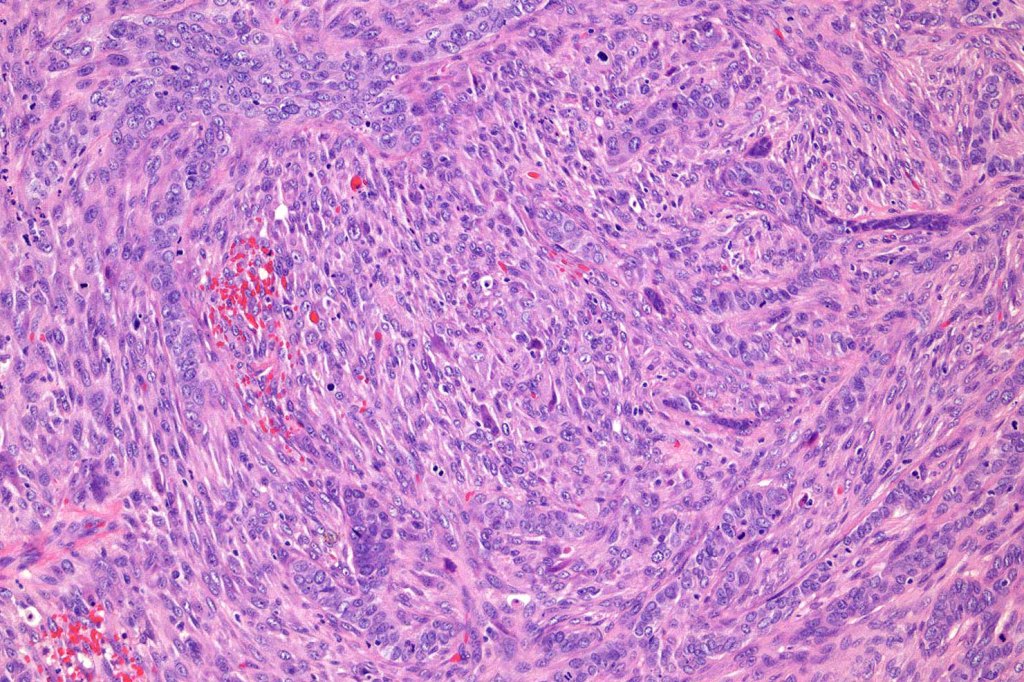

Carcinosarcoma

Cutaneous carcinosarcoma (metaplastic carcinoma, carcinoma with heterologous differentiation)

Histological features

•Osteoid

•Chondroid

•Smooth muscle

•MFH-like features with osteoclasts

•Neural differentiation